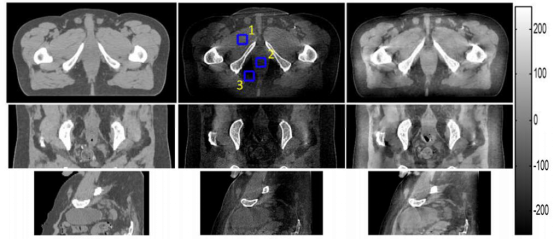

3. 面向特定医疗目标的放射影像组学研究

现代医学影像技术的发展为疾病的治疗提供了大量临床证据,治疗技术也面向个性化治疗的目标发展,结合机器学习和人工智能技术,人们可以从医学图像中提出高通量的定量特征,并且结合基因等其它医学特征进行分析,得到更加精准的治疗方案,因此诞生了近几年才提出的放射影像组学(radiomics)方向,并迅速发展,如今已经成为当前医学影像研究中的热点方向。

图像所在这个研究方向上与国内一些主要教学型医学有良好的合作关系,针对肾癌基因变异预测、肺癌放疗后的转移预测等方面取得了有益的成果,同时也在不断地开拓针对其它疾病的研究工作。有兴趣的同学可以联系我们参与该项目的研究工作,以此学习医学影像处理、诊断和机器学习等方面的相关知识,拓展自己的能力范围,提升解决问题的能力。